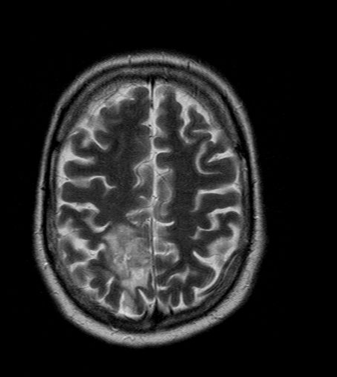

The method of choice for the imaging of multiple sclerosis is MRI. MS lesions secondary to their increased water content appear as increased signal intensity lesions on (T2 weighted), PD images and on FLAIR sequence.